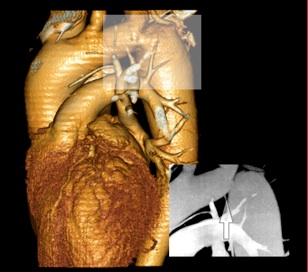

*  Darstellung und Ausmessung der  Aorta